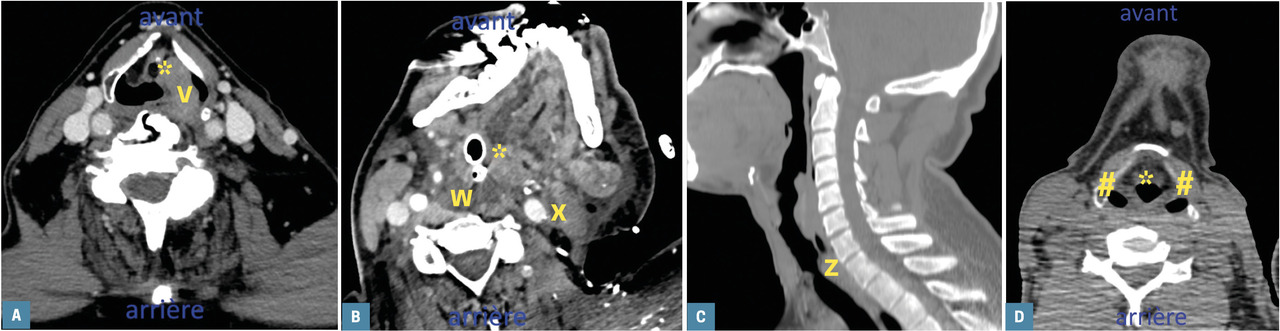

Les causes tumorales et inflammatoires sont les plus fréquentes (tableau) avec, en tête, les carcinomes épidermoïdes pharyngolaryngés (2 A ).

Les causes tumorales et inflammatoires sont les plus fréquentes (tableau) avec, en tête, les carcinomes épidermoïdes pharyngolaryngés (